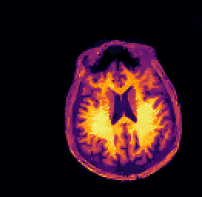

In multi-modality imaging one is often in possession of a specific piece of prior knowledge, namely a side information v𝑣v which is known to have some “common structure” with the true solution u𝑢u of the inverse problem [4]. The literature on this topic is rich with some works as early as the 1990’s so we only list a couple of key papers here. For instance, v𝑣v could be a high-resolution photograph which assists the reconstruction of low-resolution hyperspectral images [5, 6, 7, 8, 9] or an anatomical (MRI or CT) image for the reconstruction of PET images [10, 11, 12, 13, 14, 15, 16, 17], see Figure 2. This strategy has also been used for functional MRI (fMRI) [18], spectral CT [19], electrical impedance tomography (EIT) [20] and multi-contrast MRI [21, 22, 23, 24, 25, 26].

While these approaches can greatly improve the image reconstruction, they all assume that the target solution u𝑢u and the side information v𝑣v are perfectly aligned. If they are badly aligned, most of these methods yield unsatisfactory reconstructions, see Figure 2 for an illustration. In real-world applications such misalignment typically cannot be avoided since frequently the acquisitions of v𝑣v and f𝑓f happen at different times and through different modalities, see e.g. [27].

Refer to captionPET sinogram data

Refer to captionreconstruction withPgaligned side info

Refer to captionreconstruction withPgmisaligned side info

Figure 2: While reconstruction with structural side information (center) can yield very good reconstructions even for noisy data (left), the reconstruction is completely distorted when the side information is misaligned (right).